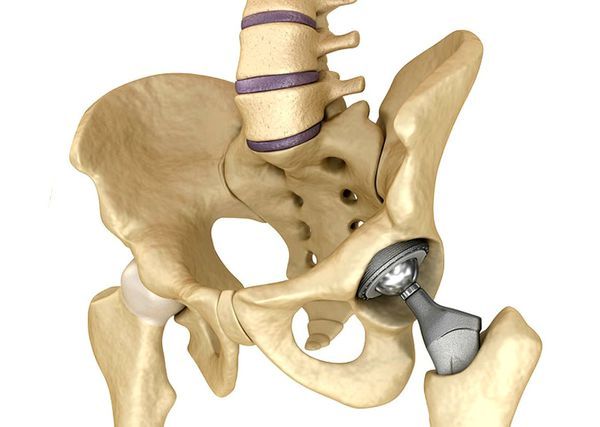

Эндопротезирование тазобедренного сустава

При развитии артроза 3-й стадии показано оперативное лечение — тотальное эндопротезирование тазобедренного сустава, при котором заменяют сразу обе суставные поверхности: головку бедренной кости и вертлужную впадину. Даже при развитии осложнений такая операция показывает хорошие результаты: она облегчает боль, восстанавливает опорность ноги и улучшает качество жизни.

Тотальное эндопротезирование